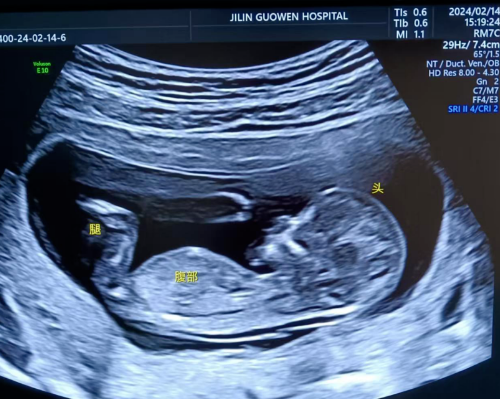

超聲檢查,孕婦無(wú)需空腹。檢查時(shí),超聲醫(yī)生會(huì)使用超聲儀器對(duì)胎兒頸部進(jìn)行仔細(xì)觀察和測(cè)量。通過(guò)超聲探頭可以清晰地看到胎兒在子宮內(nèi)的情況,重點(diǎn)測(cè)量胎兒頸項(xiàng)部皮下無(wú)回聲透明層最厚的部位,測(cè)量值即為 NT 值。正常胎兒 NT 值一般不超過(guò) 2.5mm。